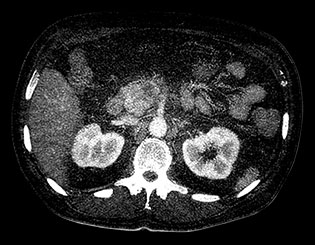

View an anatomical area using different spectral results.

Created by removing the iodine component from the image. Hounsfield Unit (HU) measurements from virtual non-contrast spectral results are comparable to true non-contrast scans for the majority of the organs, allowing VNC results to replace a true non-contrast scan.